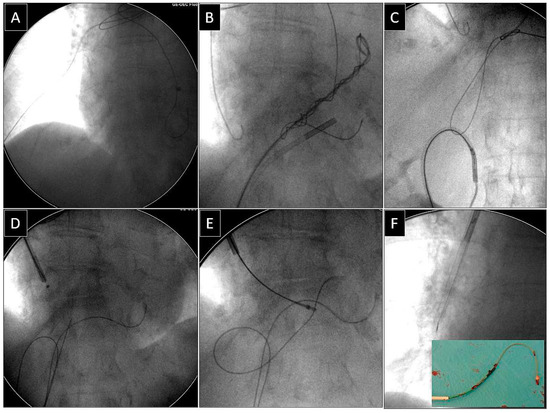

Extraction of Leads with Migrated Proximal Ends into the Cardiovascular Space